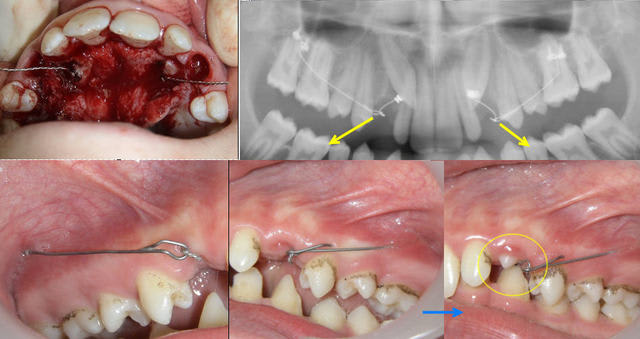

Voici déjà la n°2

Il ne restera plus qu'une seule petite erreur dans cette série. Qui la trouvera ?

je confirme que pour la 2 j'ai du repondre vite,

les couronnes des canines etant nettement plus gros que les autres dents

elles sont bien palatines et non pas vestibulaires

la théorie reste donc valable

(mais les radios sont petites !)